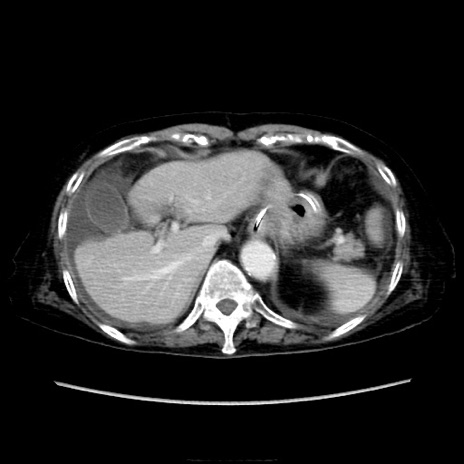

症例40(横断像)

【症例】90歳代女性

【主訴】腹痛・嘔吐

【現病歴】 食欲低下、嘔吐があり昨日他院受診。肺炎と診断され入院となる。入院後より腹部全体に圧痛あり。胃管留置され経過みていたが、症状持続するため、

当院転院となる。

【既往歴】胸椎圧迫骨折、胆石症

【身体所見】腹部:中央に激痛あり、圧痛あり、反跳痛不明

【データ】WBC 17100、CRP 18.82

横断像